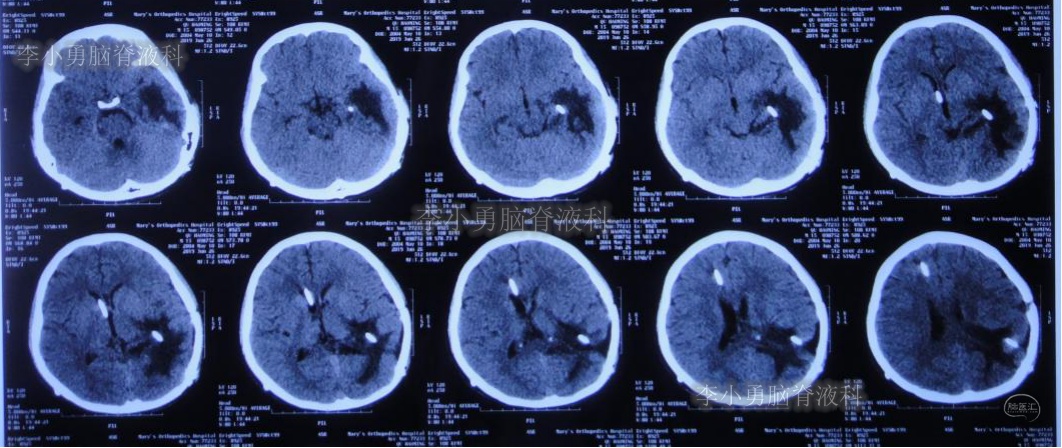

左侧颞角引流术后20天即2019年7月17日,复查头颅CT(图-21):左侧颞角积水消失,水肿消退;患者记忆力也逐渐好转。

图-21:2019年7月17日头颅CT:左侧颞角积水消失,水肿消退

左侧颞角引流术后33天即2019年8月1日,给予试夹闭右侧脑室外引流管,闭管前复查头颅CT(图-22)。

图-22:2019年8月1日夹闭前复查头颅CT